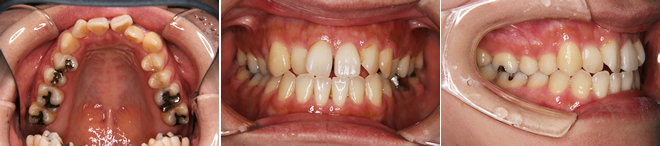

| 主訴 | 前歯の隙間が気になる |

| 年齢・性別 | 42歳 / 女性 |

| 治療方針 | 咬合力により上顎前歯が前方に傾斜したと思われるケース。元に戻りやすいため過蓋咬合をしっかり治して、保定には固定式のリテーナーも併用する。 |

| 抜歯部位 | 非抜歯 |

| 使用装置 | マルチブラケット装置 |

| 治療期間 | 16か月 |

| リテーナー | 上顎インビジブル、フィックス、下顎インビジブル |

| 費用 | 765,000円(税別) |